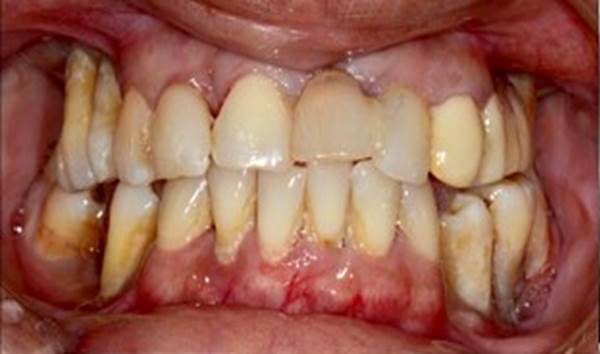

Clinical case: Extraction of all teeth in upper maxilla,

immediate implant placement, & provisionalization

- Courtesy of Dr. Iulian Filipov, Romania -

“AnyRidge ensures long-term biological stability

& functionality even in

full-mouth rehabilitation case. ”